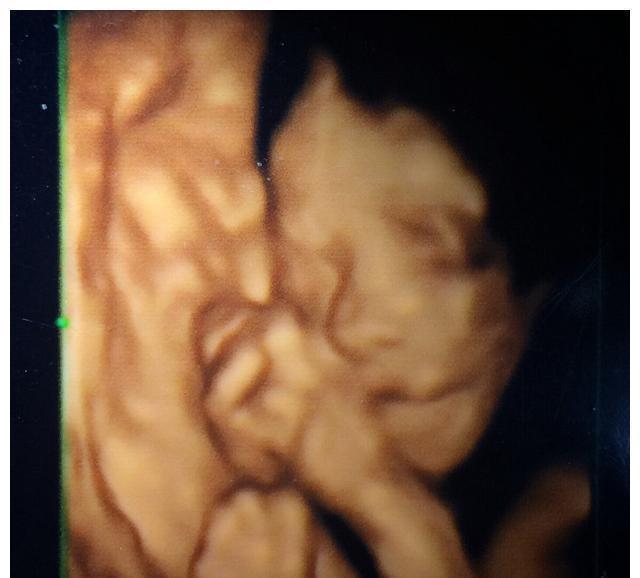

可以说这是我们和孩子的第一次“正式见面”。

如果在此之前我们对孩子还是“一无所知”的话那么做四维就是让我们和孩子第一次建立起了比较明确的链接。

我家大宝做四维时睁开了眼睛很多朋友说这不可能在羊水里怎么可能睁开眼睛

可报告图片上确实是睁着眼睛的。

由此我对老公说这孩子将来可能会比较敏感和早熟很可能是超声波的噪音打扰了他所以他睁了一下眼睛正好这一瞬间被保存了下来。

宝爸们要珍惜这第一次和孩子“见面”的机会说不定会一下子唤起内心父爱的火苗。

有些私立医院做四维的时候宝爸可以陪同检查检查的地方还会有一个放大的显示屏可以让宝爸宝妈更能看清孩子的样子还可以看到孩子在肚子里的各种动作。有些医院还会把四维彩超做成光盘留给爸爸妈妈做纪念。